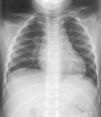

Se solicitó una radiografía de tórax, la cual se muestra en la figura 2.

Figura 2. Radiografía de tórax.

Costilla cervical

En la radiografía de tórax (fig. 2) se pueden contar 13 costillas a cada lado, debido a la presencia de una costilla supernumeraria cervical bilateral a nivel C7. En la figura 3 se aprecian con más detalle ambas costillas cervicales, la izquierda con hipoplasia del arco anterior, que sigue un trayecto vertical y parece fusionarse con el arco posterior de la primera costilla.